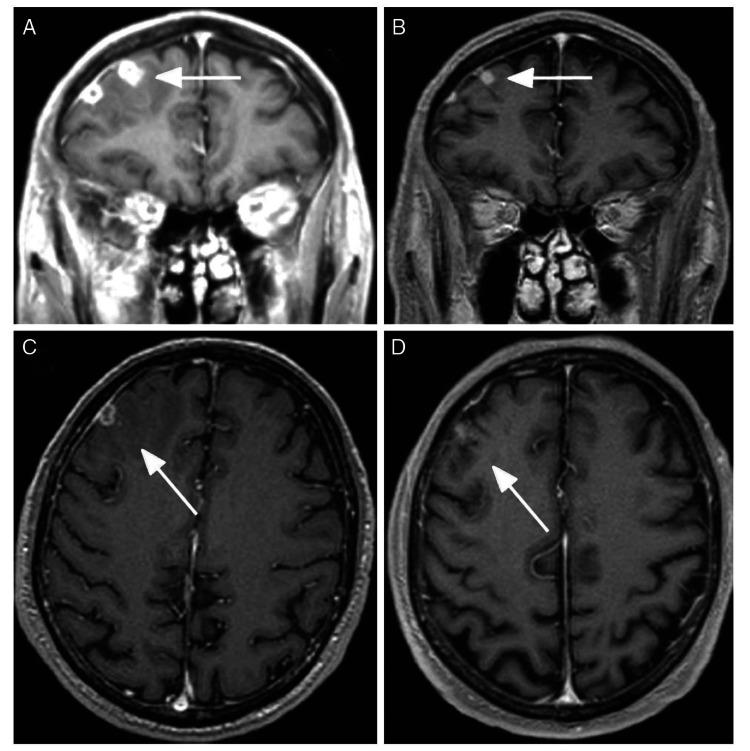

Tuberculosis is a disease caused by a bacteria named Mycobacterium tuberculosis (M. tb). It is estimated by World Health Organization (WHO) that nearly a quarter of the world's population is infected. Tuberculoma of the brain is one of the most severe extrapulmonary forms that affects patients younger than 40 years of age. Brain parenchymal tuberculoma develops in nearly one of 300 non-treated cases of pulmonary tuberculosis cases. In endemic regions, tuberculomas account for as many as 50% of all intracranial masses. Tuberculoma results in a hematogenous spread of M. tb from an extracranial source. Tuberculomas can mimic a variety of diseases and can present themselves in a subacute or chronic course, from asymptomatic to severe intracranial hypertension. Diagnosis is based on computed tomography (CT) scan and magnetic resonance imaging (MRI) studies with a similar ring-enhancing lesion. Treatment is primarily medical, and the duration for brain tuberculoma can vary from six to 36 months. In certain cases, surgery is recommended.

结核病是一种由名为结核分枝杆菌(M. tb)的细菌引起的疾病。世界卫生组织(WHO)估计,全球近四分之一的人口受到感染。脑结核瘤是影响40岁以下患者的最严重的肺外形式之一。在300例未经治疗的肺结核病例中,约有1例会发生脑实质结核瘤。在流行地区,结核瘤占所有颅内肿块的比例高达50%。结核瘤是由颅外来源的结核分枝杆菌血行播散所致。结核瘤可模仿多种疾病,可呈亚急性或慢性病程,从无症状到严重颅内高压。诊断基于计算机断层扫描(CT)和磁共振成像(MRI)检查,表现为类似的环形强化病变。治疗主要是药物治疗,脑结核瘤的疗程可从6个月到36个月不等。在某些情况下,建议进行手术。